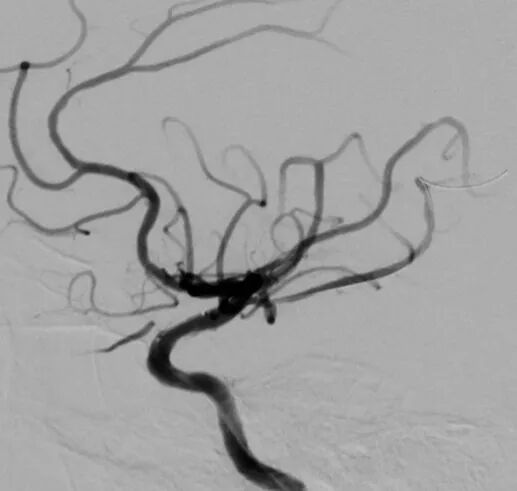

术后影像及检查

影像结论:术后残余狭窄小于 10%。

导丝怎么扩【载药时代 球扩天下】NOVA DES®颅内药物洗脱支架在颈内动脉颅内段重度狭窄中的应用体会二例!_https://www.jmylbn.com_新闻资讯_第30张

手术总结

操作体会

颅内球扩支架是主要适应于血管相对较短、较直的血管,同时无明显穿支动脉;术中微导丝远端放置需格外小心,可以考虑塑回形圈,避免前置或支撑不佳;相对于分支较少的粥样硬化狭窄患者,赛诺神畅 NOVA DES®内药物洗脱支架顺应性及支撑效果均为上佳选择。同时赛诺神畅 NOVA DES®内药物洗脱支架术后解剖影像复位较颅内自膨支架好。术后进行复查随访,与APOLLO支架以及颅内自膨支架再狭窄率进行对比。